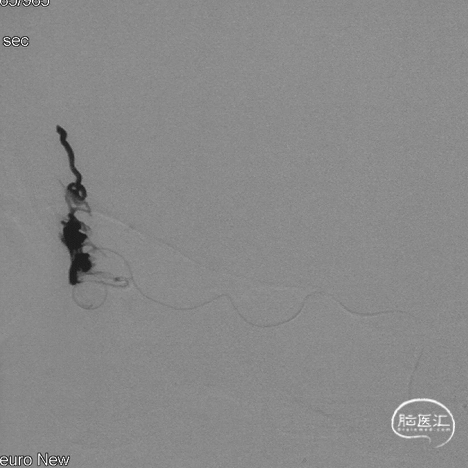

术后三个月造影复查,双侧颈内动脉、颈外动脉造影均未见静脉早显,DAVF治愈。